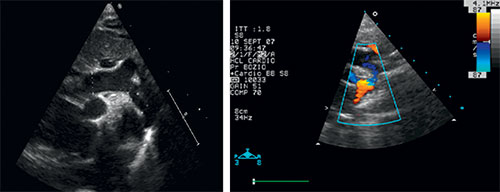

Fig. 11.1 ![]() Coarctation aortique préductale du nouveau-né : échocardiographie transthoracique.

Coarctation aortique préductale du nouveau-né : échocardiographie transthoracique.

Toute l’aorte thoracique est habituellement visible chez le petit nourrisson par voie sous-claviculaire droite ou sus-sternale. La partie transverse et l’isthme de l’aorte sont très hypoplasiques. L’aorte descendante retrouve un calibre normal en aval de l’implantation du canal artériel. L’artère subclavière gauche s’implante immédiatement en aval de la zone rétrécie.

Coarctation préductale typique bien visualisée en IRM (flèche).